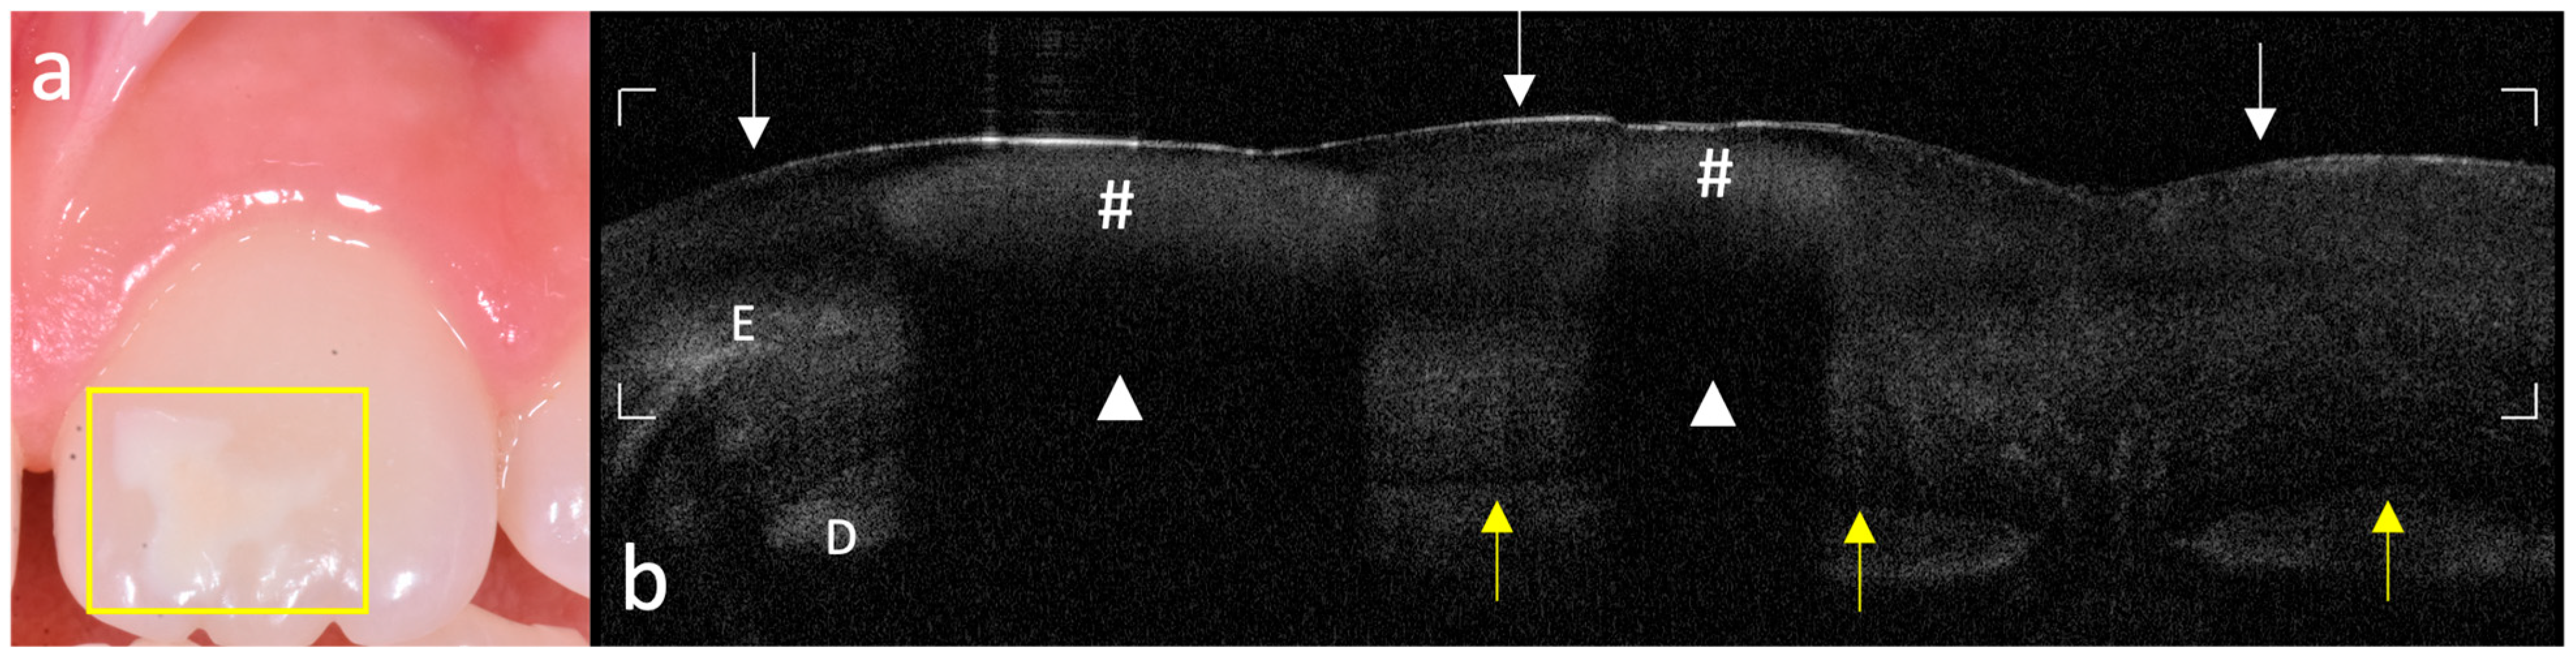

OCT imaging of teeth affected by MIH revealed structural optical patterns clearly distinct from those of sound enamel and dentin, enabling a high-resolution qualitative characterization of early enamel defects; the analysis uncovered several morphological variations with greater detail and clarity. A consistent finding in affected teeth was a discontinuous, undulating hyper-reflective band located within the outer third of the enamel (Figure 3). This band was absent in all control samples and is likely indicative of local changes in mineral density and prism organization associated with hypomineralization. Beneath this layer, deeper hypo-reflective regions were frequently observed, suggestive of subsurface porosities or microvoids that contribute to light scattering and signal attenuation.

Figure 3. Subsurface hyper-reflective band with corresponding OCT signal alterations in the underlying enamel. (a) Clinical photograph: presence of a sharply demarcated white opacity on the buccal dental surface. The yellow rectangle indicates the site of OCT acquisition; (b) corresponding OCT scan of the vestibular surface: the enamel (E) appears morphologically continuous at the surface (white arrows). A superficial hyper-reflective band consistent with hypomineralization is evident (#), overlying a subsurface hypo-reflective zone indicative of increased enamel porosity (white triangle, △). The dentino–enamel junction (DEJ) is visible as a well-defined hyper-reflective line (yellow arrows) but appears discontinuous in areas beneath hypomineralized enamel due to shadowing artifacts. The hyper-reflective band of dentin (D) is clearly distinguishable from the overlying enamel, except in regions affected by shadow cones, where it becomes less defined.